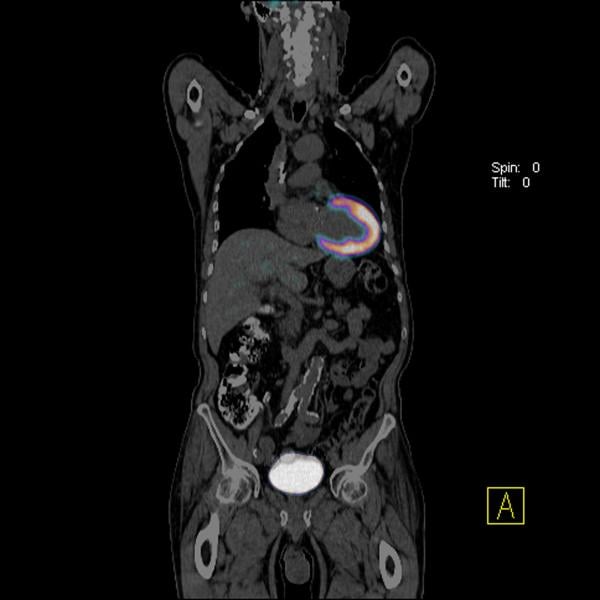

A PET-CT head and neck cancer scan showing various image reconstructions. The top left image is the separate CT scan showing the anatomy. The top right scan shows the fused PET and CT scans with false color added to help interpret the image. The bottom left scan is an initial FDG PET image showing tracer hot spots in the neck and a lymph node in the right jaw due to cancer. The right bottom image is a delayed enhancement scan showing tracer uptake over time, with normal hot spots in the bladder, kidneys, testicles and brain, which normally have higher metabolic activity. The low-grade gray shading of the anatomy is due to the normal cellular metabolism uptake of the FDG throughout the body.

A common question from patients is what is a PET-CT scanner? Today, most standalone PET imaging systems have been replaced by hybrid PET-CT (positron emission tomography - computed tomography) scanners, which combine separate PET and CT imaging systems into one gantry to allow fused, simultaneous imaging using PET and X-ray CT. The CT system offers anatomical detail and helps with attenuation correction for the PET imaging for more accurate, clearer PET image reconstructions. The overlay of fused CT images on the PET scans can help pinpoint “hot spots” of tracer uptake, such as cancerous tumors. These can be used to help make a more accurate diagnosis, aid tumor monitoring or tracking during chemotherapy, and aid in either surgical or radiation therapy planning.

The most common biologically active molecule used in PET is flurodeoxyglucose (F-18 FDG), which is an analog of glucose. It is used in about 90 percent of PET scanning in the United States. Cells in the body metabolize this sugar for energy, so high concentrations of FDG seen on PET indicate areas of high metabolic activity (as in cancer). Areas of low or no metabolic activity can indicate areas of reduced blood flow or blockages due to stroke or heart attacks. Use of FDG in full body scans can help determine if a cancer has metastasized to other areas of the body. If so, the PET scan can help pinpoint the extent of the cancer’s spread and help identify areas for further treatment or monitoring.